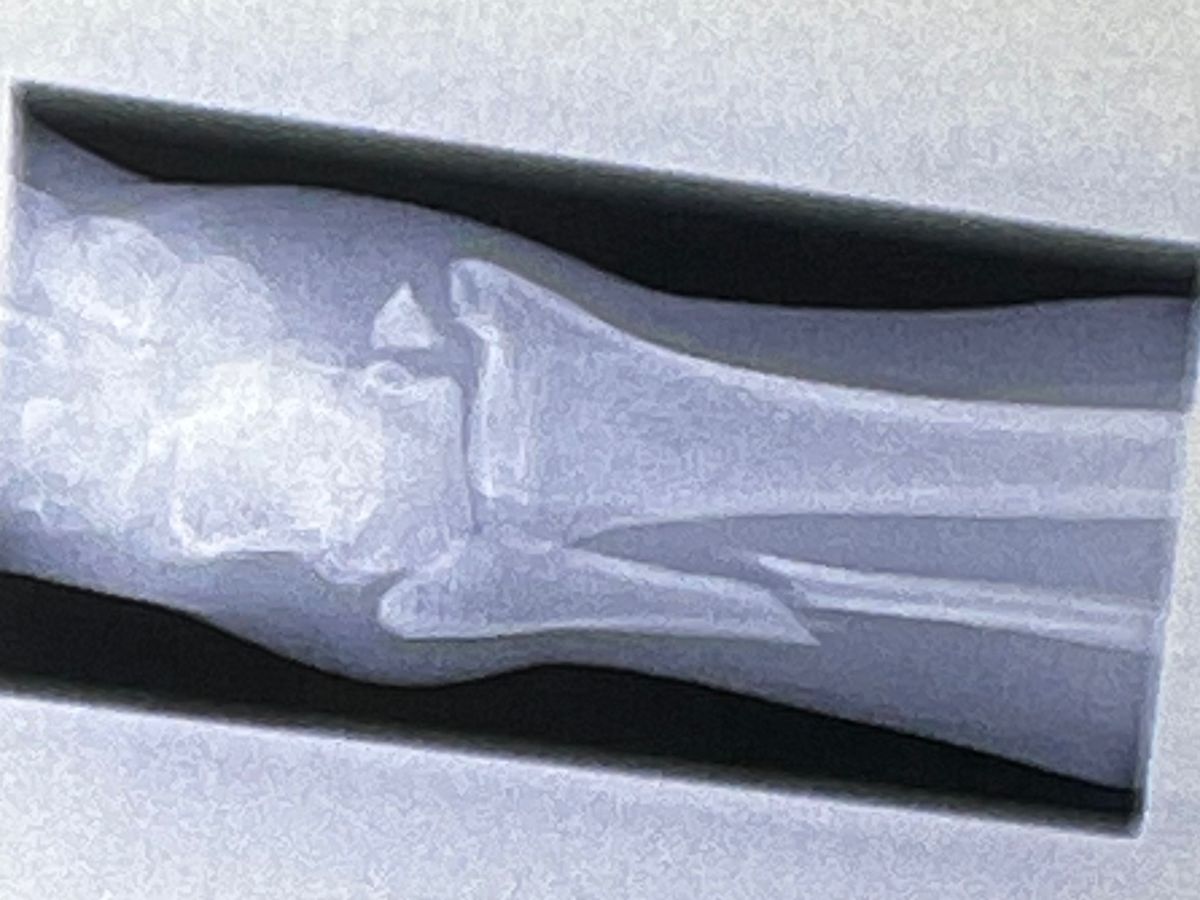

Hi, I’m Natalie and I recently broke my ankle quite severely while competing in what was supposed to be a “friendly” Judo competition. I have a trimalleolar fracture, which means my ankle is broken in 3 places and I will need surgery. I also have extensive tendon and ligament damage.